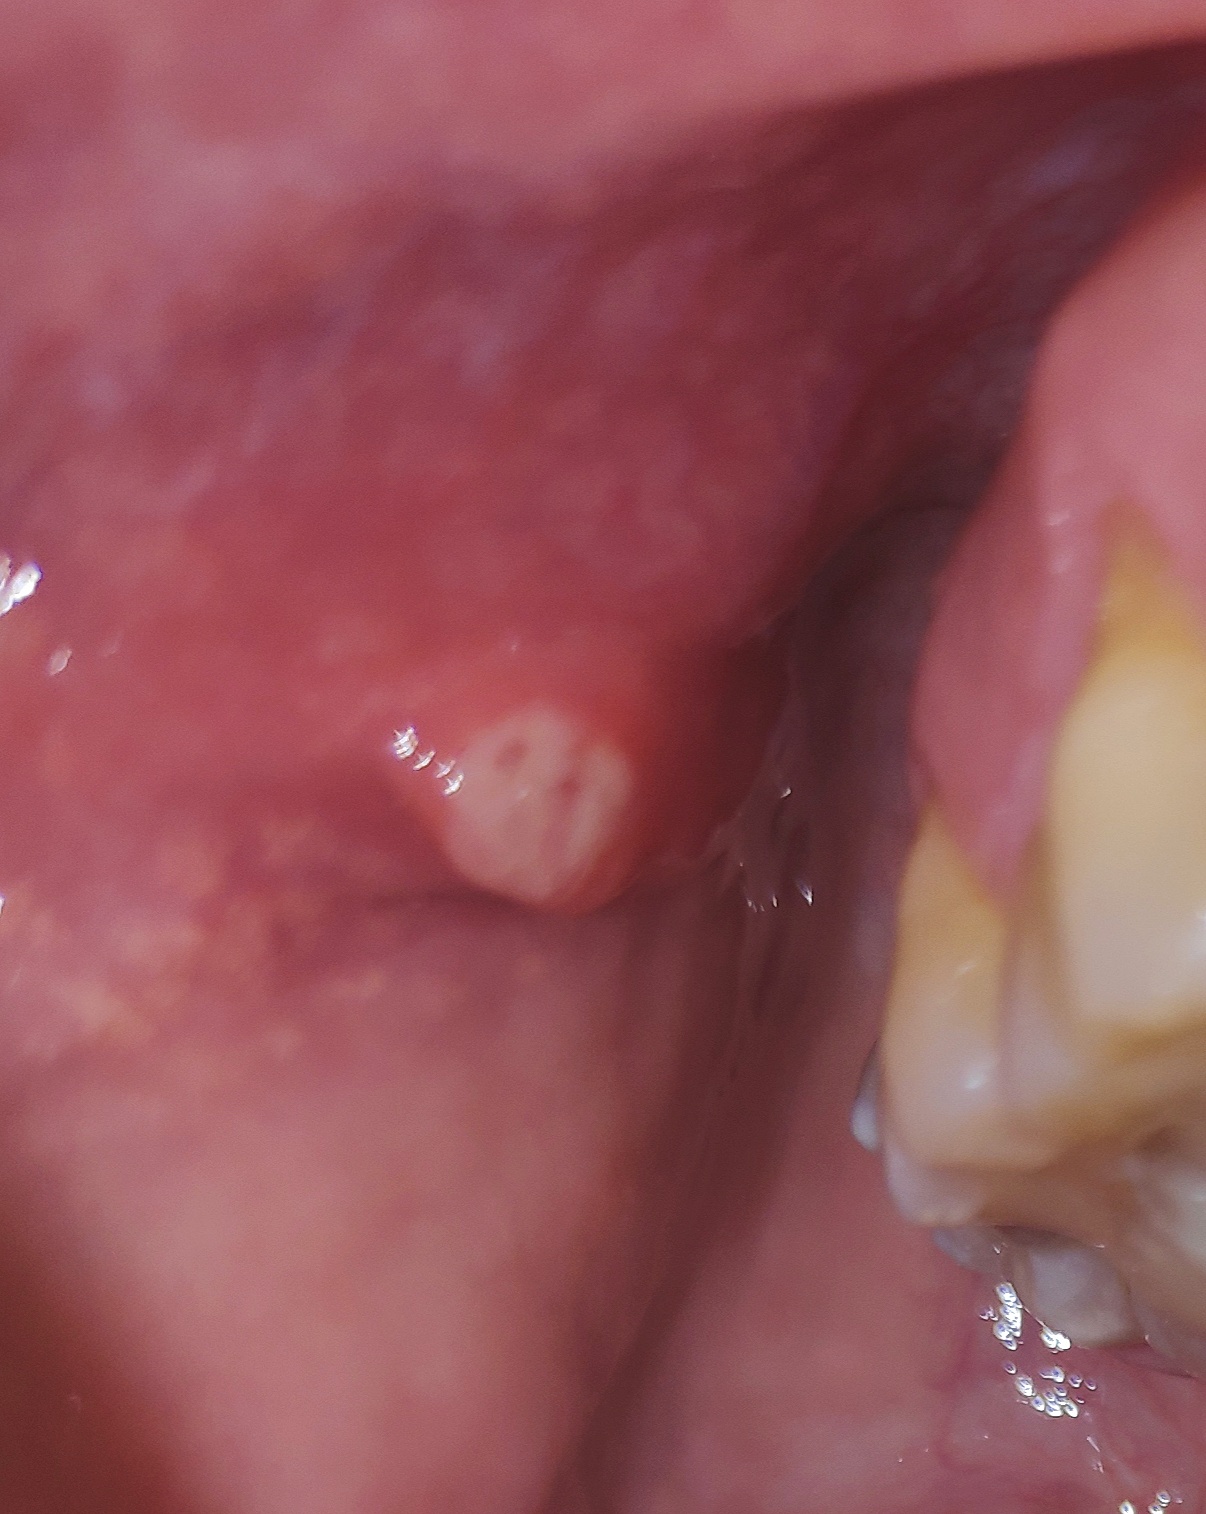

Author: Klaas Posted: do, 06/20/2019 - 22:49 Dag allemaal, Zie de foto's. Moet ik mij zorgen maken om het 'bultje' (witachtig, zacht) aan de binnenkant van mijn wang? Wat zou dit kunnen zijn? Het is duidelijk voelbaar met de tong; maar heb het pas sinds een paar dagen (opgemerkt). Vriendelijke groet, Klaas Attach Klaas Niemand? Het doet ook (een Niemand? Het doet ook (een beetje) zeer. Stuur privébericht Login of registreer om te reageren za, 06/22/2019 - 08:23 Permalink Lieneke Als antwoord op Niemand? Het doet ook (een door Klaas Niemand? Het doet ook (een Dat is je speekselklier, maar die ziet er niet gezond uit...laat er maar naar kijken. Stuur privébericht Login of registreer om te reageren ma, 07/01/2019 - 13:19 Permalink 253 weergaves

Lieneke Als antwoord op Niemand? Het doet ook (een door Klaas Niemand? Het doet ook (een Dat is je speekselklier, maar die ziet er niet gezond uit...laat er maar naar kijken. Stuur privébericht Login of registreer om te reageren ma, 07/01/2019 - 13:19 Permalink